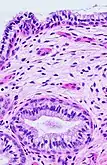

The endocervical mucosa is about 3 mm (0.12 in) thick and lined with a single layer of columnar mucous cells. It contains numerous tubular mucous glands, which empty viscous alkaline mucus into the lumen.[3] In contrast, the ectocervix is covered with nonkeratinized stratified squamous epithelium,[3] which resembles the squamous epithelium lining the vagina.[16]: 41 The junction between these two types of epithelia is called the squamocolumnar junction.[16]: 408–11 Underlying both types of epithelium is a tough layer of collagen.[17] The mucosa of the endocervix is not shed during menstruation. The cervix has more fibrous tissue, including collagen and elastin, than the rest of the uterus.[3]

The squamocolumnar junction of the cervix, with abrupt transition: The ectocervix, with its stratified squamous epithelium, is visible on the left. Simple columnar epithelium, typical of the endocervix, is visible on the right. A layer of connective tissue is visible under both types of epithelium.